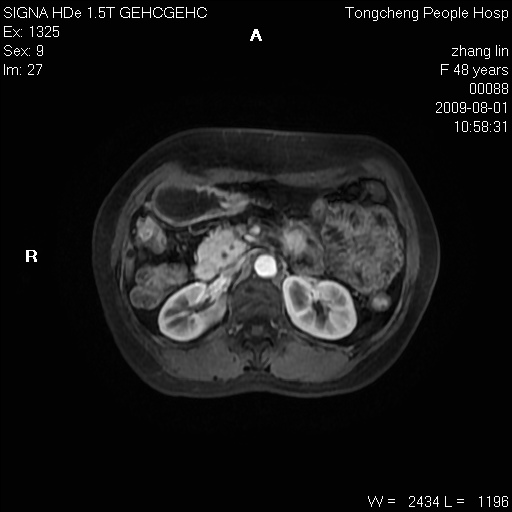

女,48岁。健康体检,彩超发现右肾占位性病变。平素健康。

临床诊断:右肾占位性病变,性质待定(囊肿?肿瘤?)。

上中腹部mr平扫+增强扫描,图像如下:

右肾上极见一类圆形病灶,t1wi呈等信号t2wi呈等高混杂信号,三期增强无强化,边界清---考虑囊肿出血。

同反相位均表现为等信号,病变无强化,考虑含蛋白的囊肿可能,弥散加权相或许有些帮助,